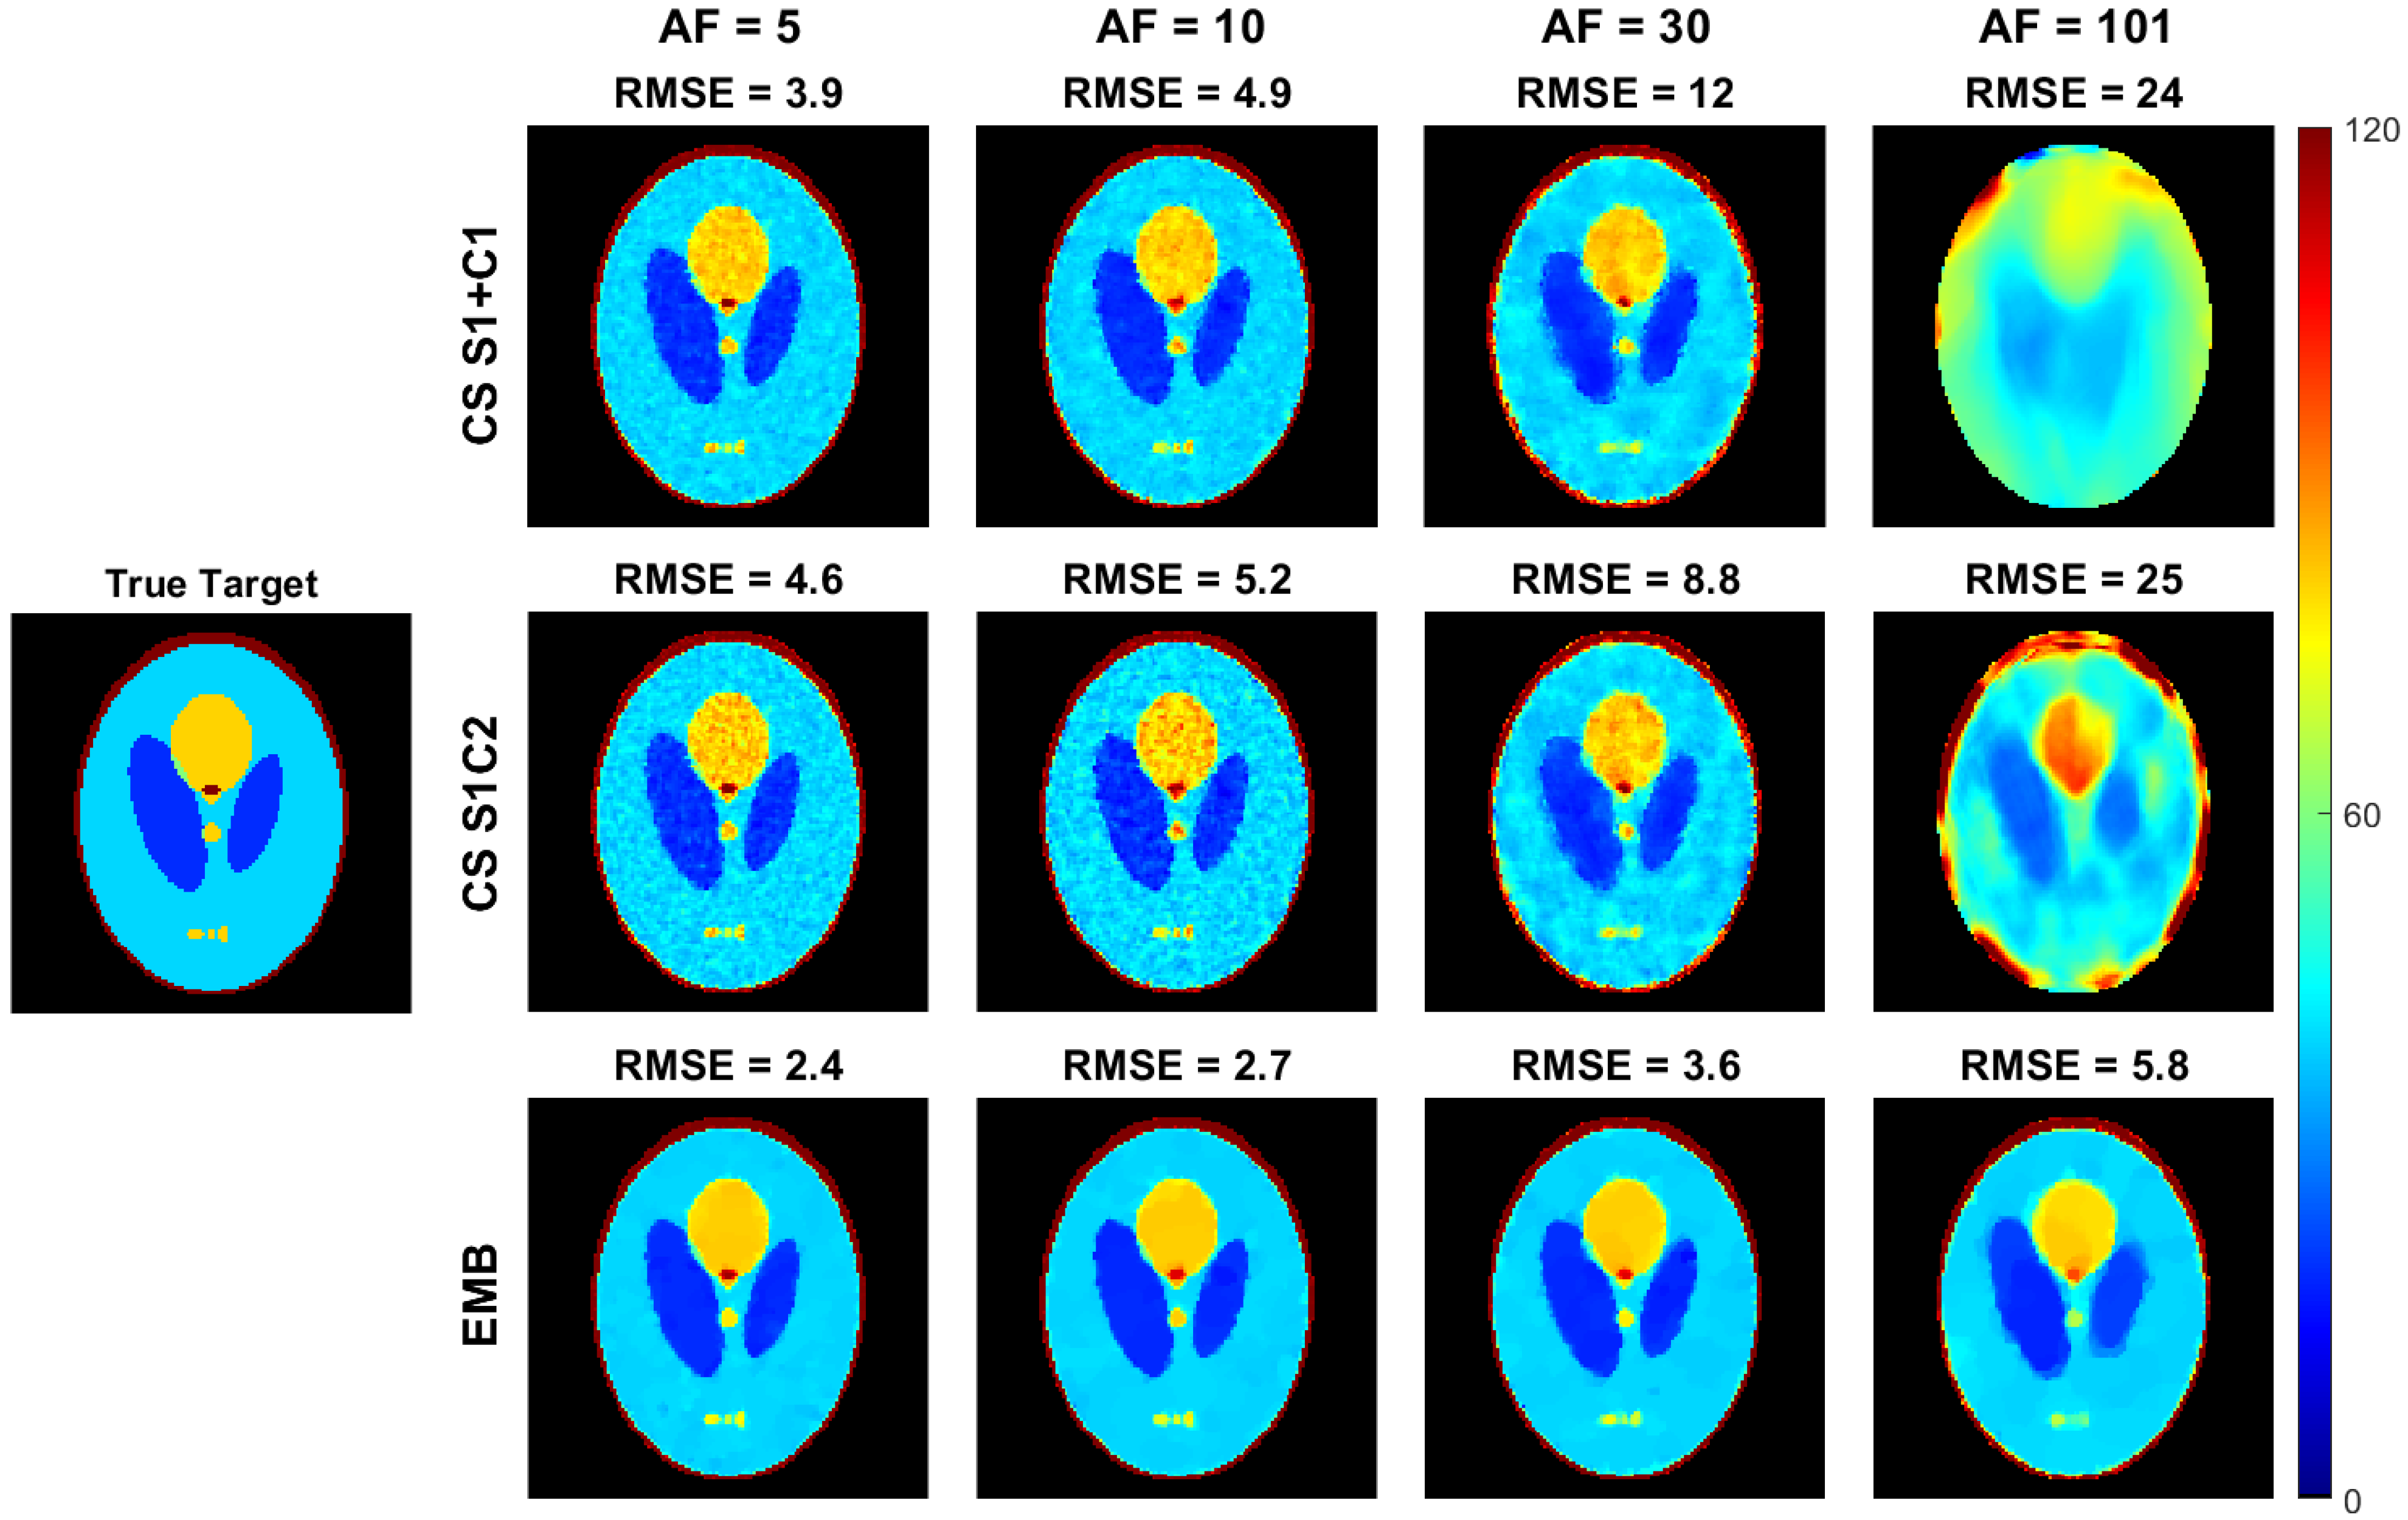

4.1. Simulated Golden Angle Radial Data